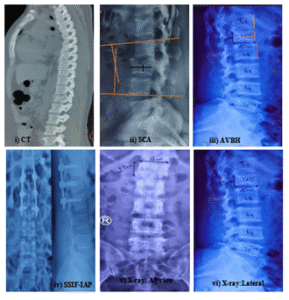

Figure 08: i) CT showing L1 Burst fracture. ii) L3 Burst fracture, SCA (Sagittal Cobbâs angle) calculation. iii) AVBH (anterior vertebral body height) calculation. iv) SSIF-IAP (short segment internal fixation with inclined angle poly axial) screw. v) X-ray: LS spine anteroposterior view. vi)X-ray: LS spine lateral view.